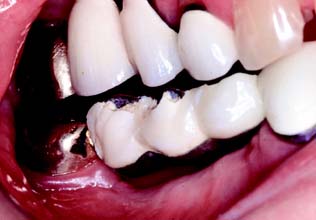

Supragingival margin placement has many biologic advantages. The restorations are easier to prepare properly and easier to keep clean. Nevertheless, subgingival margins may be indicated for esthetic reasons, particularly when the patient has a high lip line and when the use of a metal collar labial margin is contemplated.

The patient’s smile is observed as part of the initial examination (see Chapter 1). It is important to record which teeth and which parts of each tooth are exposed. Patients with a high lip line, which exposes considerable gingival tissue, present the greatest problem if complete crowns are needed. Where the root surface is not discolored, appearance can be restored with a metal-ceramic restoration with a supragingival porcelain labial margin (see Chapter 24). If the patient has a low lip line, a metal supragingival collar may be placed because the metal is not seen during normal function. Metal margins generally have a more accurate fit than porcelain margins.

However, it cannot be assumed that the patient will be happy with a supragingival metal collar just because the metal is not visible during normal function. Some patients have reservations about exposed metal, and the advantages of such supragingival margins must be carefully explained before treatment.

Metal collars can be hidden below the gingival crest, although there is some discoloration if the gingival tissue is thin. Successful margin placement within the gingival sulcus requires care to ensure that inflammation and/or recession, with resulting metal exposure, are avoided or minimized. The periodontium must be healthy before the tooth is prepared. If periodontal surgery is needed, the sulcular space should not be eliminated completely; rather, a postsurgical depth of about 2 mm should be the objective. Sufficient time should be allowed after surgery for the periodontal tissues to stabilize. Wise109 found that the gingival crest does not stabilize until 20 weeks after surgery (see Chapter 5).

Margins should not be placed so far apically that they encroach on the attachment; extension to within 1.5 mm of the alveolar crest leads to bone resorption.110 The margin should follow the contour of the free gingiva, being further apical in the middle of the tooth and further incisal interproximally. A common error (Fig. 7-51) is to prepare the tooth so the margin lies almost in one plane, with exposure of the collar labially and irreversible loss of bone and papilla proximally.

Fig. 7-51 Poor preparation design. A, These badly damaged incisors were treatment planned for metal-ceramic crowns. B and C, The apical margin of the preparation does not follow the free gingival contours. D, The restoration displays a metal collar labially, and the deep proximal margins have led to periodontal disease.